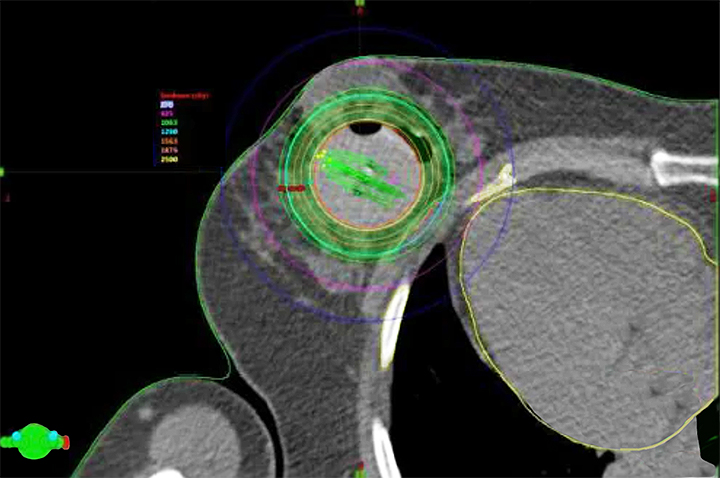

Providence Saint John’s Health Center and the Saint John’s Cancer Institute are located in the heart of sunny Santa Monica, CA. Though we are a community hospital, we function like an academic institution that provides our patients access to novel clinical trials and investigator-initiated research through the Saint John’s Cancer Institute. Our program provides exposure to advanced oncoplastic surgical approaches performed by both our surgical breast oncologists and plastic surgeons. Our breast center, strategically located next to our breast imaging and radiation oncology departments, houses two ultrasound machines in the clinic, promoting skills in ultrasound-guided localization. We also use a wireless device and wire localization to provide broad exposure to different techniques. Fellows will also have experience with Intraoperative Radiation Therapy (IORT), a technique used in breast conservation treatment.